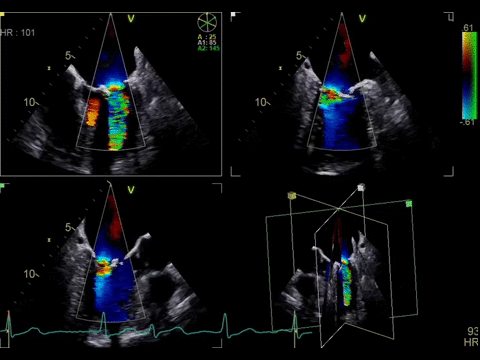

4D color imaging with the 4Vc-D probe

Color Flow